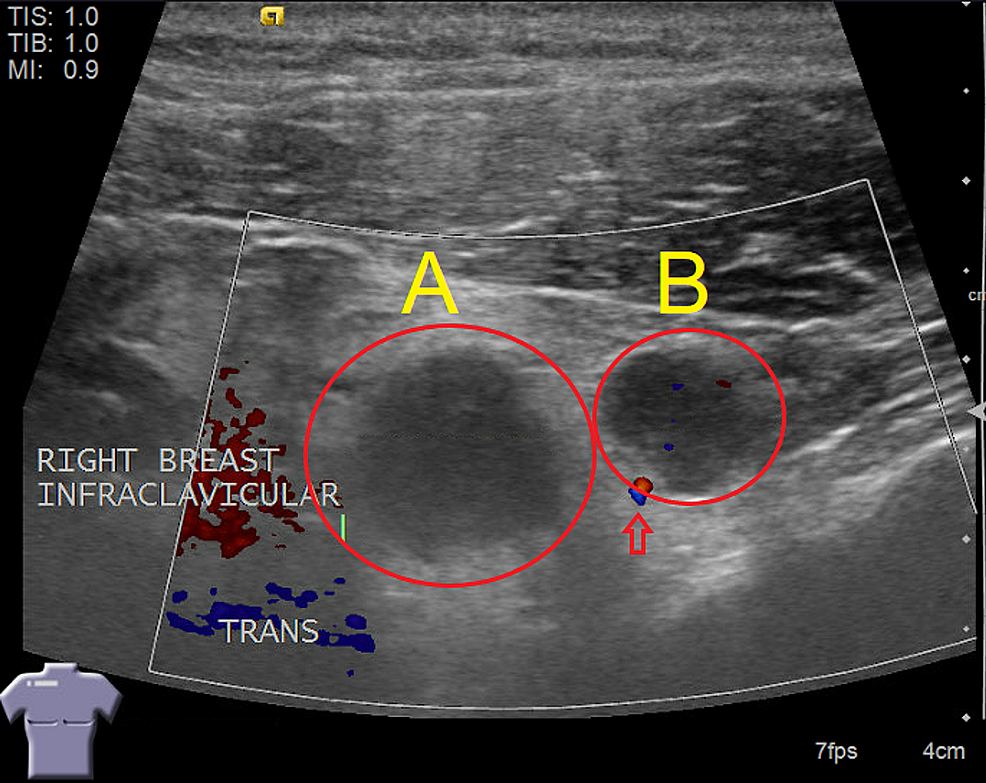

From mavink.com

Lymph Node Vs Abscess Ultrasound Abscess Tooth Lymph Node Such infections can occur due to tooth decay, gum disease, or a. Other periodontal abscess symptoms may include: A dental abscess can travel to the brain. Tooth abscesses develop in response to acquiring a bacterial infection inside the tooth, gums, or jaw bone. The lymph nodes act as filters for the fluids, and the lymphocytes produced within the lymph nodes. Abscess Tooth Lymph Node.

Lymph Node Vs Abscess Ultrasound Abscess Tooth Lymph Node Periapical abscess symptoms may include: Teeth sensitivity to hot or cold foods and beverages. Such infections can occur due to tooth decay, gum disease, or a. Once there, it can develop another abscess, known as a. Tender or swollen lymph nodes in the neck or jaw area can also be a sign of a tooth abscess. An abscess is the. Abscess Tooth Lymph Node.